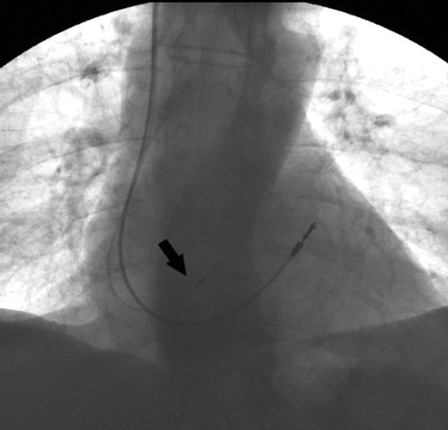

Учитывая наличие у пациента постоянной формы ФП, артифициальной атриовентрикулярной блокады 3-й степени, постоянную электрокардиостимуляцию, а также клинические жалобы, пациенту показано оперативное лечение в виде замены ЭКС и имплантации электрода в область пучка Гиса. Отметим, что изобретение электрода с активной фиксацией Medtronic SelectSecure 3830 и системы доставки Medtronic SelectSite C304 позволило сделать методику более рутинной. В первую очередь нами был осуществлен доступ в правой бедренной вене по Сельдингеру и установлен интродьюсер. Затем проведено картирование кольца трикуспидального клапана под флюороскопическим контролем. Мы использовали электрофизиологический катетер для картирования с целью точного определения местоположения проводящей системы. Катетером выполняли поиск электрограммы пучка Гиса, что было критерием для фиксации спирали электрода в эту область. Изображение с локализацией пучка Гиса дублировалось на дополнительный монитор. Для поиска пучка Гиса применялся также метод униполярного картирования. Вторым этапом выполняли доступ к ЭКС, тестирование прежних электродов и венозный доступ (головная, подключичная или подмышечная вена) (рис. 2). Система доставки Medtronic SelectSite C304 предварительно моделировалась в теплом физиологическом растворе с целью обеспечения септального изгиба для позиционирования электрода в область перегородки. Система доставки заводилась в сердце по проводнику к кольцу трикуспидального клапана. Доставка позиционировалась в верхней части кольца клапана, вблизи области пучка Гиса. Контрастирование полостей сердца не проводилось. Затем электрод продвигался к кончику доставки в монополярной конфигурации. Кончик доставки находился в непосредственном контакте с перегородкой. После того как было отмечено соотношение электрограмм предсердий и желудочков 1:2, доставку направили в сторону перегородки минимальным вращением против часовой стрелки. Для картирования и стимуляции следует использовать электрокардиограмму с 12 отведениями. Как только местоположение Гиса определено, доставку необходимо удерживать неподвижно левой рукой, а электрод медленно вращать по часовой стрелке 5 раз. Очень важный момент – количество попыток вкручивания электрода. В нашем случае электрод был позиционирован со второго раза. После этого доставку вытянули назад, а электрод осторожно протягивали вперед, пока в предсердии не сформировалась петля. Предпочтительно тестирование при длительности импульса 1 мс, чтобы обеспечить более низкий порог. У большинства пациентов порог стимуляции пучка Гиса составляет 2,0 В в 1 мс. В нашем случае порог стимуляции был 3,6 В при длительности импульса 1,5 мс, стимуляционный импеданс – 669 Ом. Как только приемлемый порог был достигнут, доставка была разрезана и удалена. Электроды коммутированы с ЭКС His – A, RV-RV (рис. 3). Вектор QRS идентичен нативному. Базовая частота была 60 имп/мин в биполярном режиме стимуляции (режим DDD(R), атриовентрикулярная задержка 100 мс). Длительность операции составила 140 минут, длительность радиационного облучения – 5 минут. Эффективная доза облучения – 0,025 мЗв [7].

Рис. 3. Рентгенограмма после имплантации. Отражено два электрода: прежний, установленный в выходном тракте правого желудочка, и новый, имплантированный в область пучка Гиса (указан стрелкой)